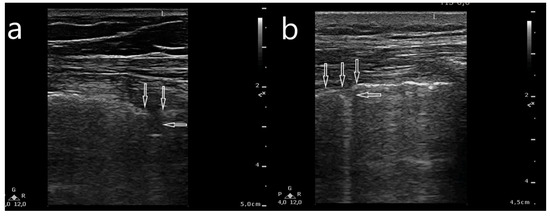

- (3)

- Consolidations: small subpleural consolidations (up to 5 mm) accompanied with C-line artifacts, large consolidations involving segments and/or lobes, pleural effusion.